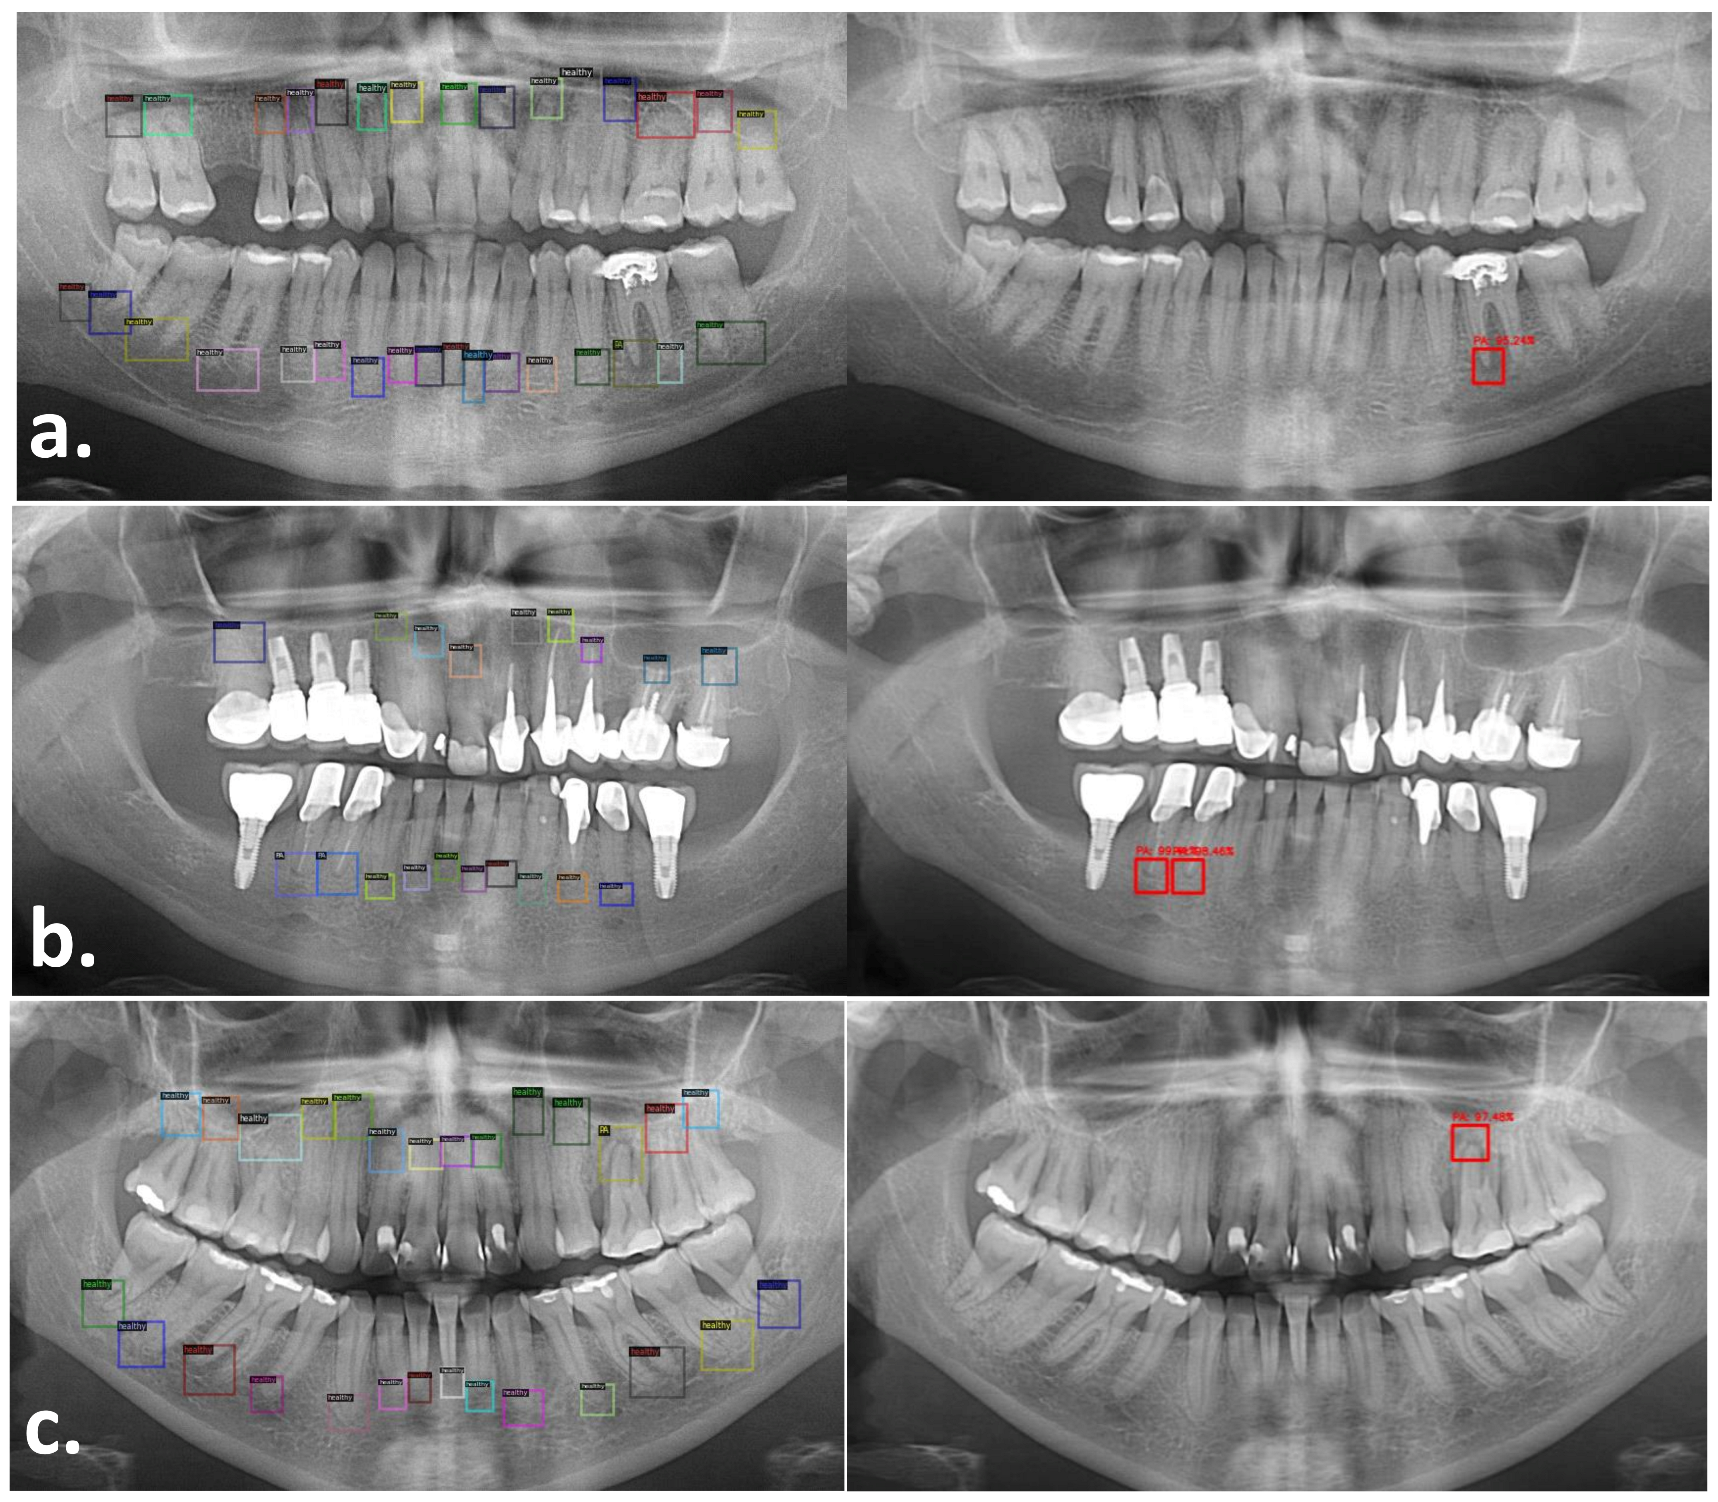

Our proposed detector identified the PRAs using a custom function based on the model aster R-RCNN. We tested two strategies to train our detector. In the first strategy (method 1) we only included unhealthy PRA (PL) for the training, while for the second strategy (method 2) we included both healthy (H) and unhealthy (PL). We trained for 1000 iterations and evaluated the detection performance of both methods based on Average Precision (AP) calculated at intersection-over-union (IOU) =0.5 on a test set of 143 images. Method 1 achieved AP50 of 38.5% while method 2 achieved AP50 of 74.95% at iteration 1000. We observed that training the detector on PRAs including H and PL classes achieved faster convergence and higher detection rates. We therefore adopted this approach in our further experiments. The proposed system then cropped and normalized all predicted bounding boxes that were then submitted to the classifier model. Figure 2 shows one example of the output of the detection model. The detector was able to adapt to the size and extension of the periapical region automatically depending on the size and extension of the roots and the lesions. This was demonstrated by the high AP50 of the algorithm. Each periapical area was labeled independently regardless of whether it was found on single rooted or multi rooted teeth.

Figure 2. Detection of periapical areas (PRA) on panoramic radiograph by clinicians and by the AI. First image: OPG showing the PRA annotated by the expert clinician. Second image: OPG showing the proposed PRA generated by the detection model for the same image. All PRAs were detected by the proposed model (Faster RCNN).